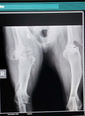

Man wollte ihn einschläfern, weil der Tierarzt meinte, er würde nicht mehr laufen können! Er hatte eine Schussverletzung in der Schulter. Wir haben ihn in letzter Minute gerettet. Inzwischen ist er wieder so weit genesen, hat aber eine mehr oder minder leichte Gehbehinderung zurückbehalten. Die Ärzte vor Ort sagten mehr kann man nicht tun. Ein einstündiger Spaziergang reicht ihm, dann möchte er wieder nach Hause. Ein Leben in einem Haus mit Garten bei Rentnern, die auch gerne einfach Zeit in ihrem Garten verbringen und kleine Spaziergänge genießen. Er ist lebensfroh und glücklich. Er lebt ihm Hier und Jetzt und scheint damit auch sehr gut klarzukommen.